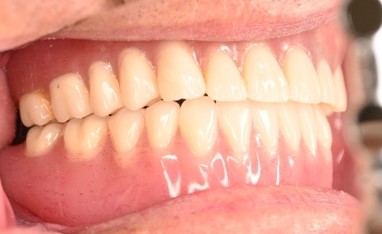

Before

赤丸は抜歯しました。上4本、下3本

After

【義歯を装着したところ】

【義歯を外したところ】